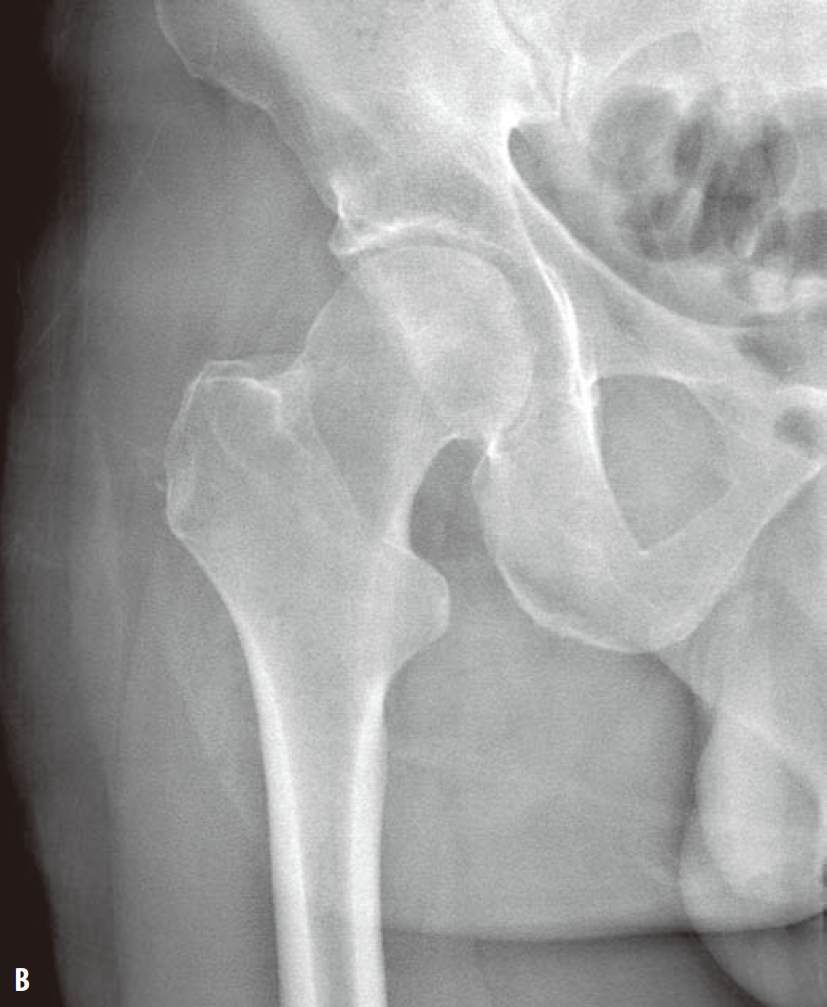

髓关节撞击综合征(femoroacetabular-impingement,FAI)是引起髋关节疼痛及髋关节进行性退行性变的一种常见病因。一般采用骨盆X线前后位照片筛查。骨盆照片时X线中心线应对准尾骨中心及耻骨联合,以保证骨盆不旋转。FAI主要分为3种类型:凸轮型、钳型和混合型。混合型FAI同时具有凸轮型和钳型的异常。凸轮型是股骨头颈连接处形成/发育异常所致,表现为股骨头颈连接处骨性隆起或“枪柄样”改变(缺乏正常的凹度)(图1)。钳型FAI表现为髋臼覆盖或位置异常,可根据在X线平片上见到深髋臼、髋臼前突或髋臼后倾的表现而诊断。深髋臼及髋臼前突X线表现为股骨头及髋臼相对髂骨坐骨线位置异常(图2)。髋臼后倾表现为交叉征、髋臼后壁征、坐骨棘突出征(图3)。

图1 左髋关节蛙式侧位X线片(A)显示股骨头、颈连接处异常隆起(箭),该骨质异常可引起凸轮型FAI。右髋关节前后位X线片(B、C)显示“枪柄样”畸形,其中旋转90°后的前后位X线片(C)可更直观地显示肌骨近端及股骨头所形成的“旧式手枪枪把”样外观